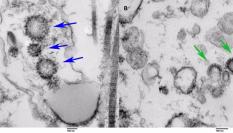

Las autopsias encontraron ARN del SARS-CoV-2 y de varias proteínas en el cerebro y la nasofaringe, y partículas de virus intactas en la nasofaringe.

Los niveles más altos de ARN viral se encontraron en la membrana mucosa olfativa, donde están las células nerviosas y reside el sentido del olfato, según el estudio.

Los autores también encontraron proteínas del SARS-CoV-2 (la que permite liberar el genoma viral en el interior de la célula que va a infectar) en ciertos tipos de células de la capa mucosa olfatoria, donde el virus podría aprovechar la proximidad del tejido endotelial y nervioso para entrar en el cerebro.

En algunos pacientes se encontró esta proteína del SARS-CoV-2 en células que expresan marcadores de neuronas, lo que sugiere que las neuronas del olfato podrían estar infectadas, al igual que otras zonas del cerebro que reciban señales olfativas y gustativas.